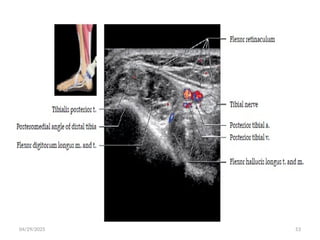

04/29/2025 22

• It passes inferiorly between the heads of gastrocnemius and

deep to soleus muscle.

• Continues inferiorly in the midline deep to soleus and

superficial to the tibialis posterior muscle.

• At the ankle passes under flexor retinaculum in the tarsal

tunnel.

04/29/2025 23

04/29/2025 24

04/29/2025 25

04/29/2025 26

• At the level of medial malleolus it divides into three terminal

branches.

1.medial plantar nerve

2.lateral plantar nerve

3.medial calcaneal nerve

 Ultrasound

 Use high-frequency transducers to assess nerves.

 Short axis: A typical “honeycomb” appearance with hypoechoic

fascicles and surrounding echogenic perineurium

 Long axis: Parallel hypoechoic tracts of uniform caliber.

 Distortion of this uniform appearance suggests pathology